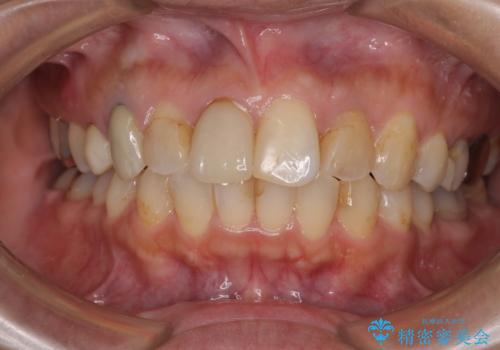

- 上下前歯のデコボコを気にして来院された患者様です。

歯列としては、ワイヤー装置でもインビザラインでも、どちらでも対応可能でしたが、処置されている歯が多く、ワイヤー装置を装着するためには処置歯のやり直しが必要な状態でした。

インビザラインでもアタッチメントを装着できないという同様のデメリットがありますが、比較的矯正治療を行いやすい歯列であったので、インビザラインによる矯正治療を行うこととしました。

術中や仕上がりに特に大きなトラブルはなく、スムーズに治療を終えることができました。